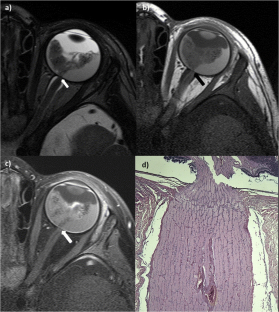

Fig. 2

High-resolution MRI using orbit surface coils for the evaluation of metastatic risk factors in 143 children with retinoblastoma

Part 1: MRI vs. histopathology

Sensitivity/specificity for the detection of metastatic risk factors using high-resolution MRI with orbit surface coils were 60 %/88.7 % for postlaminar optic nerve infiltration, 65.5 %/95.6 % for choroidal invasion, 100 %/99.3 % for scleral invasion, and 100 %/100 % for peribulbar fat invasion, respectively. The results increased for the detection of advanced metastatic risk factors, 81.8 %/89.1 % for deep postlaminar optic nerve infiltration, 70.6 %/97.6 % for massive choroidal invasion.